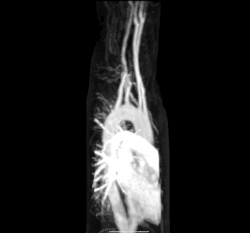

Насыщенная кислородом кровь поступает в большой круг кровообращения при выходе из левого желудочка через аортальный клапан[15]. Первой частью большого круга кровообращения является аорта, массивная и толстостенная артерия. Аорта изгибается и разветвляется, снабжая кровью верхнюю часть тела, пройдя через аортальное отверстие диафрагмы на уровне десятого грудного позвонка, входит в брюшную полость[16]. Затем ветви аорты спускаются в живот, таз, промежность и нижние конечности[17] .

Стенки аорты эластичны. Эта эластичность помогает поддерживать кровяное давление[18]. По мере того как аорта разветвляется на более мелкие артерии, их эластичность продолжает снижаться, а растяжимость увеличивается[18].